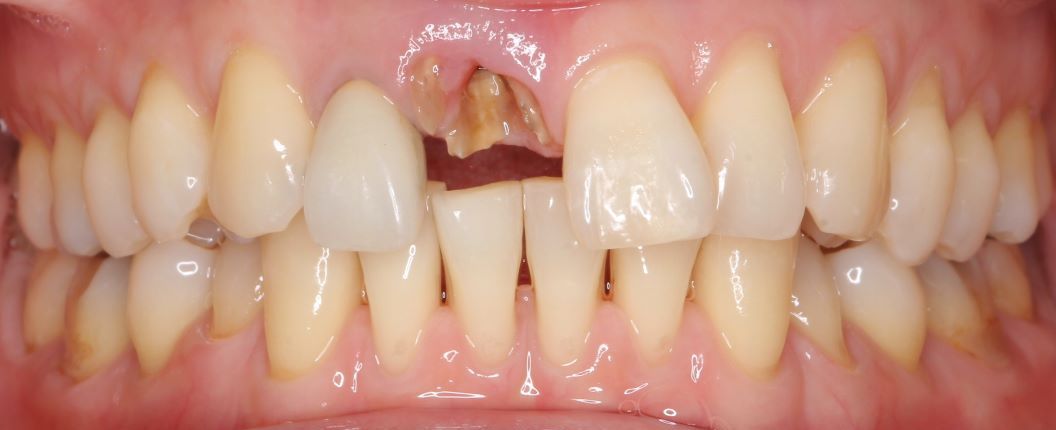

case 02.

BEFORE

AFTER

見た目を重視した治療を希望されている

(リスク)